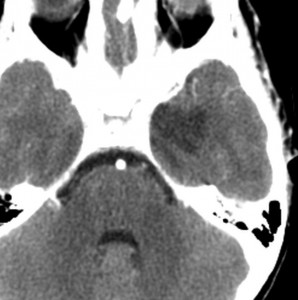

症候性てんかんのみで発症した右側頭葉と島回のグレード2オリゴです。左のT2,中央のフレアではグレード2びまん性星細胞腫と鑑別はできません。認知機能などは正常でした。

何と言っても診断的価値があるのは 石灰化 carcification です。左のCTの中央にみえる白い部分が石灰化です。この程度の石灰化でも診断的な価値があります。1p/19q codeletionがあるオリゴでした。病理では,均一な小型の円形核を有する細胞と多数の毛細血管 chickin-wire network がみられます。部分摘出後,放射線治療とテモゾロマイド化学療法でコントロールできています。